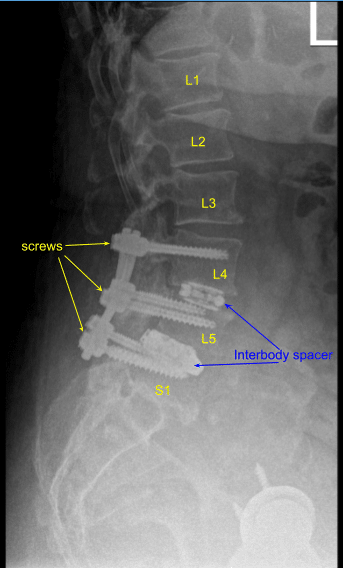

Interbody spaces were irrigated clear, packed with morselized autograft from the decompression as well as demineralized bone matrix allograft, and then an expandable titanium interbody spacer was placed under sterilely draped fluoroscopic guidance in AP and lateral views into proper position. Neuromonitoring signals were stable. Bilateral L3-4 neurolysis was performed with Metzenbaum-Penfield technique and confirmed with nerve hook circumferentially.

The wounds were irrigated clear. Precut-precontoured titanium rods were selected and placed across the tulips from L3 to L5 bilaterally and secured with locking caps which were all final tightened with a torque and anti torque device.

Bilateral transverse processes were decorticated with electric high-speed drill from L3 to L5 and morselized autograft and allograft mixed with bone marrow aspirate from a separate incision at the superior iliac crest was all combined for the posterolateral arthrodesis graft as well as bone morphogenic protein. No CSF leak or durotomy was appreciated after inspecting the thecal sac.